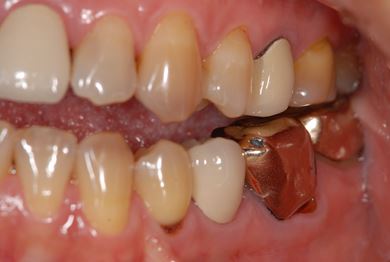

治療内容 メタルボンドセラミック(クラウン1本、ブリッジ3本、メタルボンドセラミック土台1本)+ハイブリッドセラミックインレー1本

治療部位

7 6 5 4